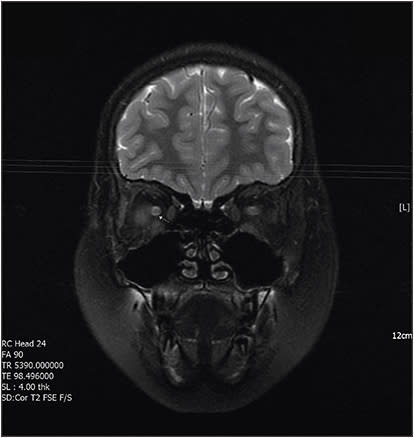

Gadolinium-enhanced MRI demonstrated increased T2W signal intensity in the nerve sheath of the right optic nerve (Figure 3, page 56), without a space-occupying mass or demyelination in the brain parenchyma. A pediatric neurologist was consulted, and optic neuritis in the right eye was diagnosed.

Figure 3. Gadolinium-enhanced brain MRI demonstrated increased T2W signal intensity in the nerve sheath of right optic nerve without space occupying mass or demyelination in the brain parenchyma.